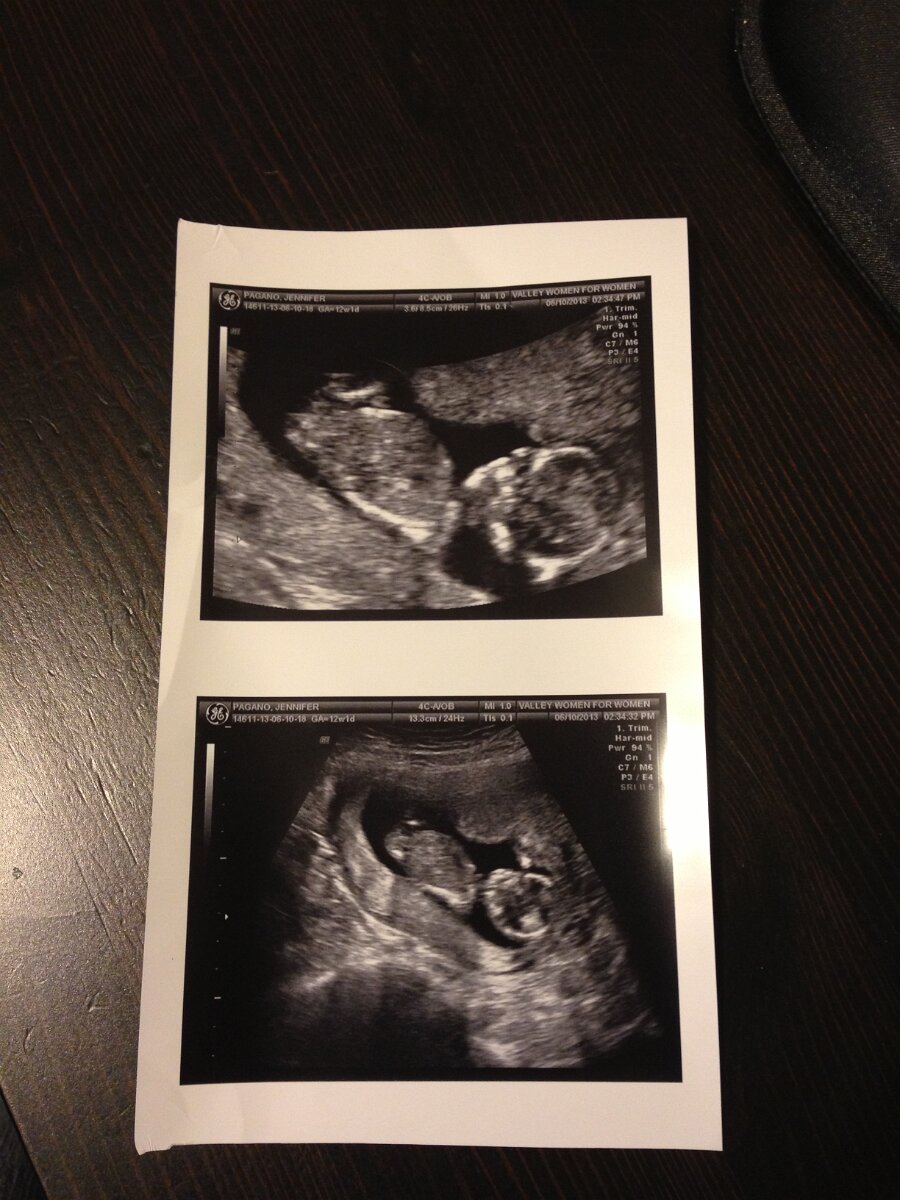

2013-06-10

June 10th

Our Baby